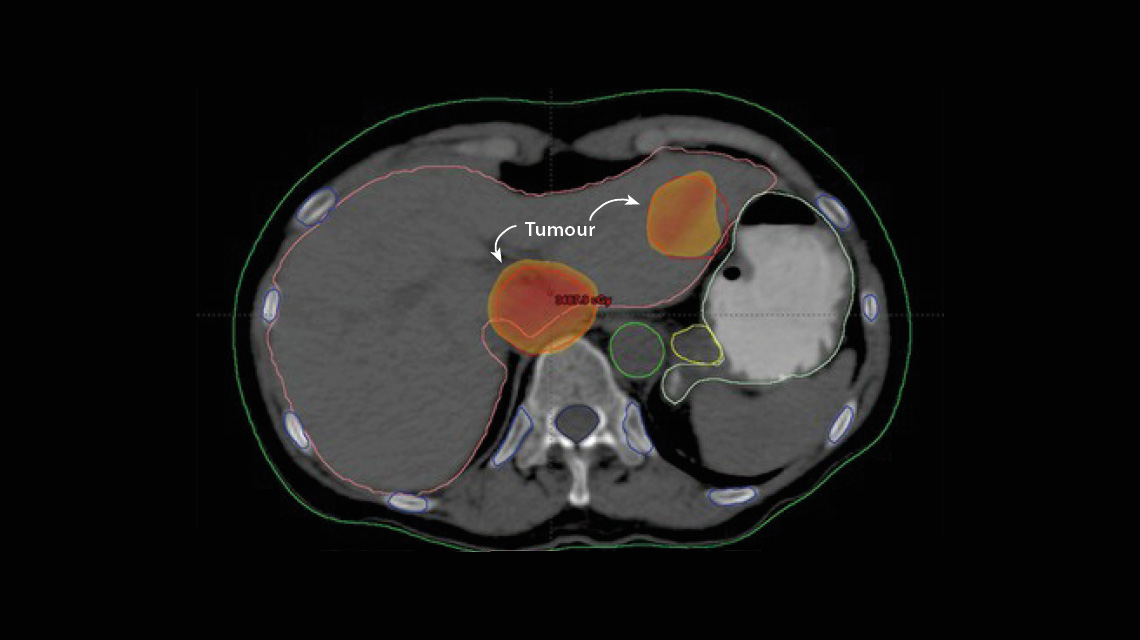

Лечение рака печени с использованием современного метода лучевой терапии — стереотаксической радиотерапии всего тела.(Фото: Национальный институт рака, Египет)

Благодаря СРВТ удалось достичь нового уровня контроля и точности при лечении. Эта технология уникальна, поскольку предусматривает создание четырехмерных моделей, отражающих высоту, ширину, глубину и в некоторых случаях динамику, что позволяет с высокой точностью планировать лазерную терапию и воздействовать на опухоль пучками излучения под разными углами. Каждый пучок содержит меньшую дозу излучения: это более безопасно и позволяет снизить риск побочных эффектов для здоровой ткани, через которую проходит излучение. Когда все пучки излучения сходятся на опухоли в одной точке, раковые клетки подвергаются большей суммарной дозе облучения. В целом это означает, что для эффективного лечения пациенту требуется меньше сеансов лучевой терапии.

Шуман пояснил, что методы лучевой терапии для лечения рака печени, в частности ГЦК, были коренным образом усовершенствованы благодаря применению СРВТ. Сегодня рак печени занимает третье место в мире по числу летальных исходов среди всех видов рака. На протяжении многих лет эффективное лечение этого вида рака с применением методов лучевой терапии было невозможным: традиционная лучевая терапия не позволяет безопасно использовать дозы излучения, достаточно высокие для лечения опухоли печени, из-за риска поражения прилегающих здоровых тканей печени. СРВТ может использоваться для лечения даже самых небольших опухолей печени с применением увеличенных доз излучения без вреда для здоровой ткани.